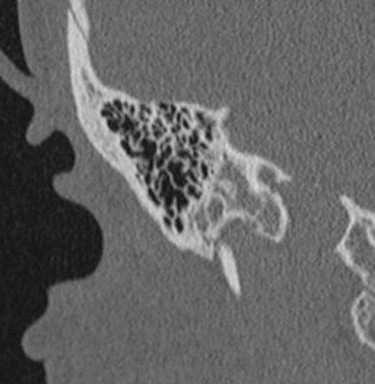

2. КТ при интралабиринтной шванноме:

• КТ без КУ:

о Обычно норма, ИЛШ не видна

• КТ с КУ:

о ИЛШ не видна даже на тонкосрезовой КТ с КУ

• КТ в костном окне:

о Норма, за исключением случаев, когда опухоль пролабирует в среднее ухо через нишу круглого окна

о При очень больших опухолях (трансмодиолярных, трансмакулярных, трансотических) могут обнаруживаться костные эрозии

о КТ в костном окне обычно не позволяет сделать заключение об ИЛШ